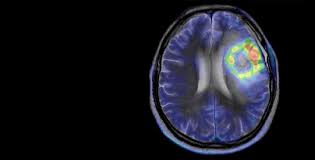

Часто контраст применяется при ПЭТ/КТ исследовании головного мозга. Изображения, получаемые при помощи позиционно-эмиссионного томографа под разными углами, регистрируют наличие опухоли. Сделать диагностику более точной в этом случае помогает внутривенное введение препаратов йода. Такое исследование поможет отличить рецидив заболевания от послеоперационных осложнений, возникающих при удалении опухоли. ПЭТ/КТ, дополненная введением контрастного вещества, отображает процессы, протекающие в головном мозге, метаболизм глюкозы и кислорода, кровообращение и работу специфических рецепторов.